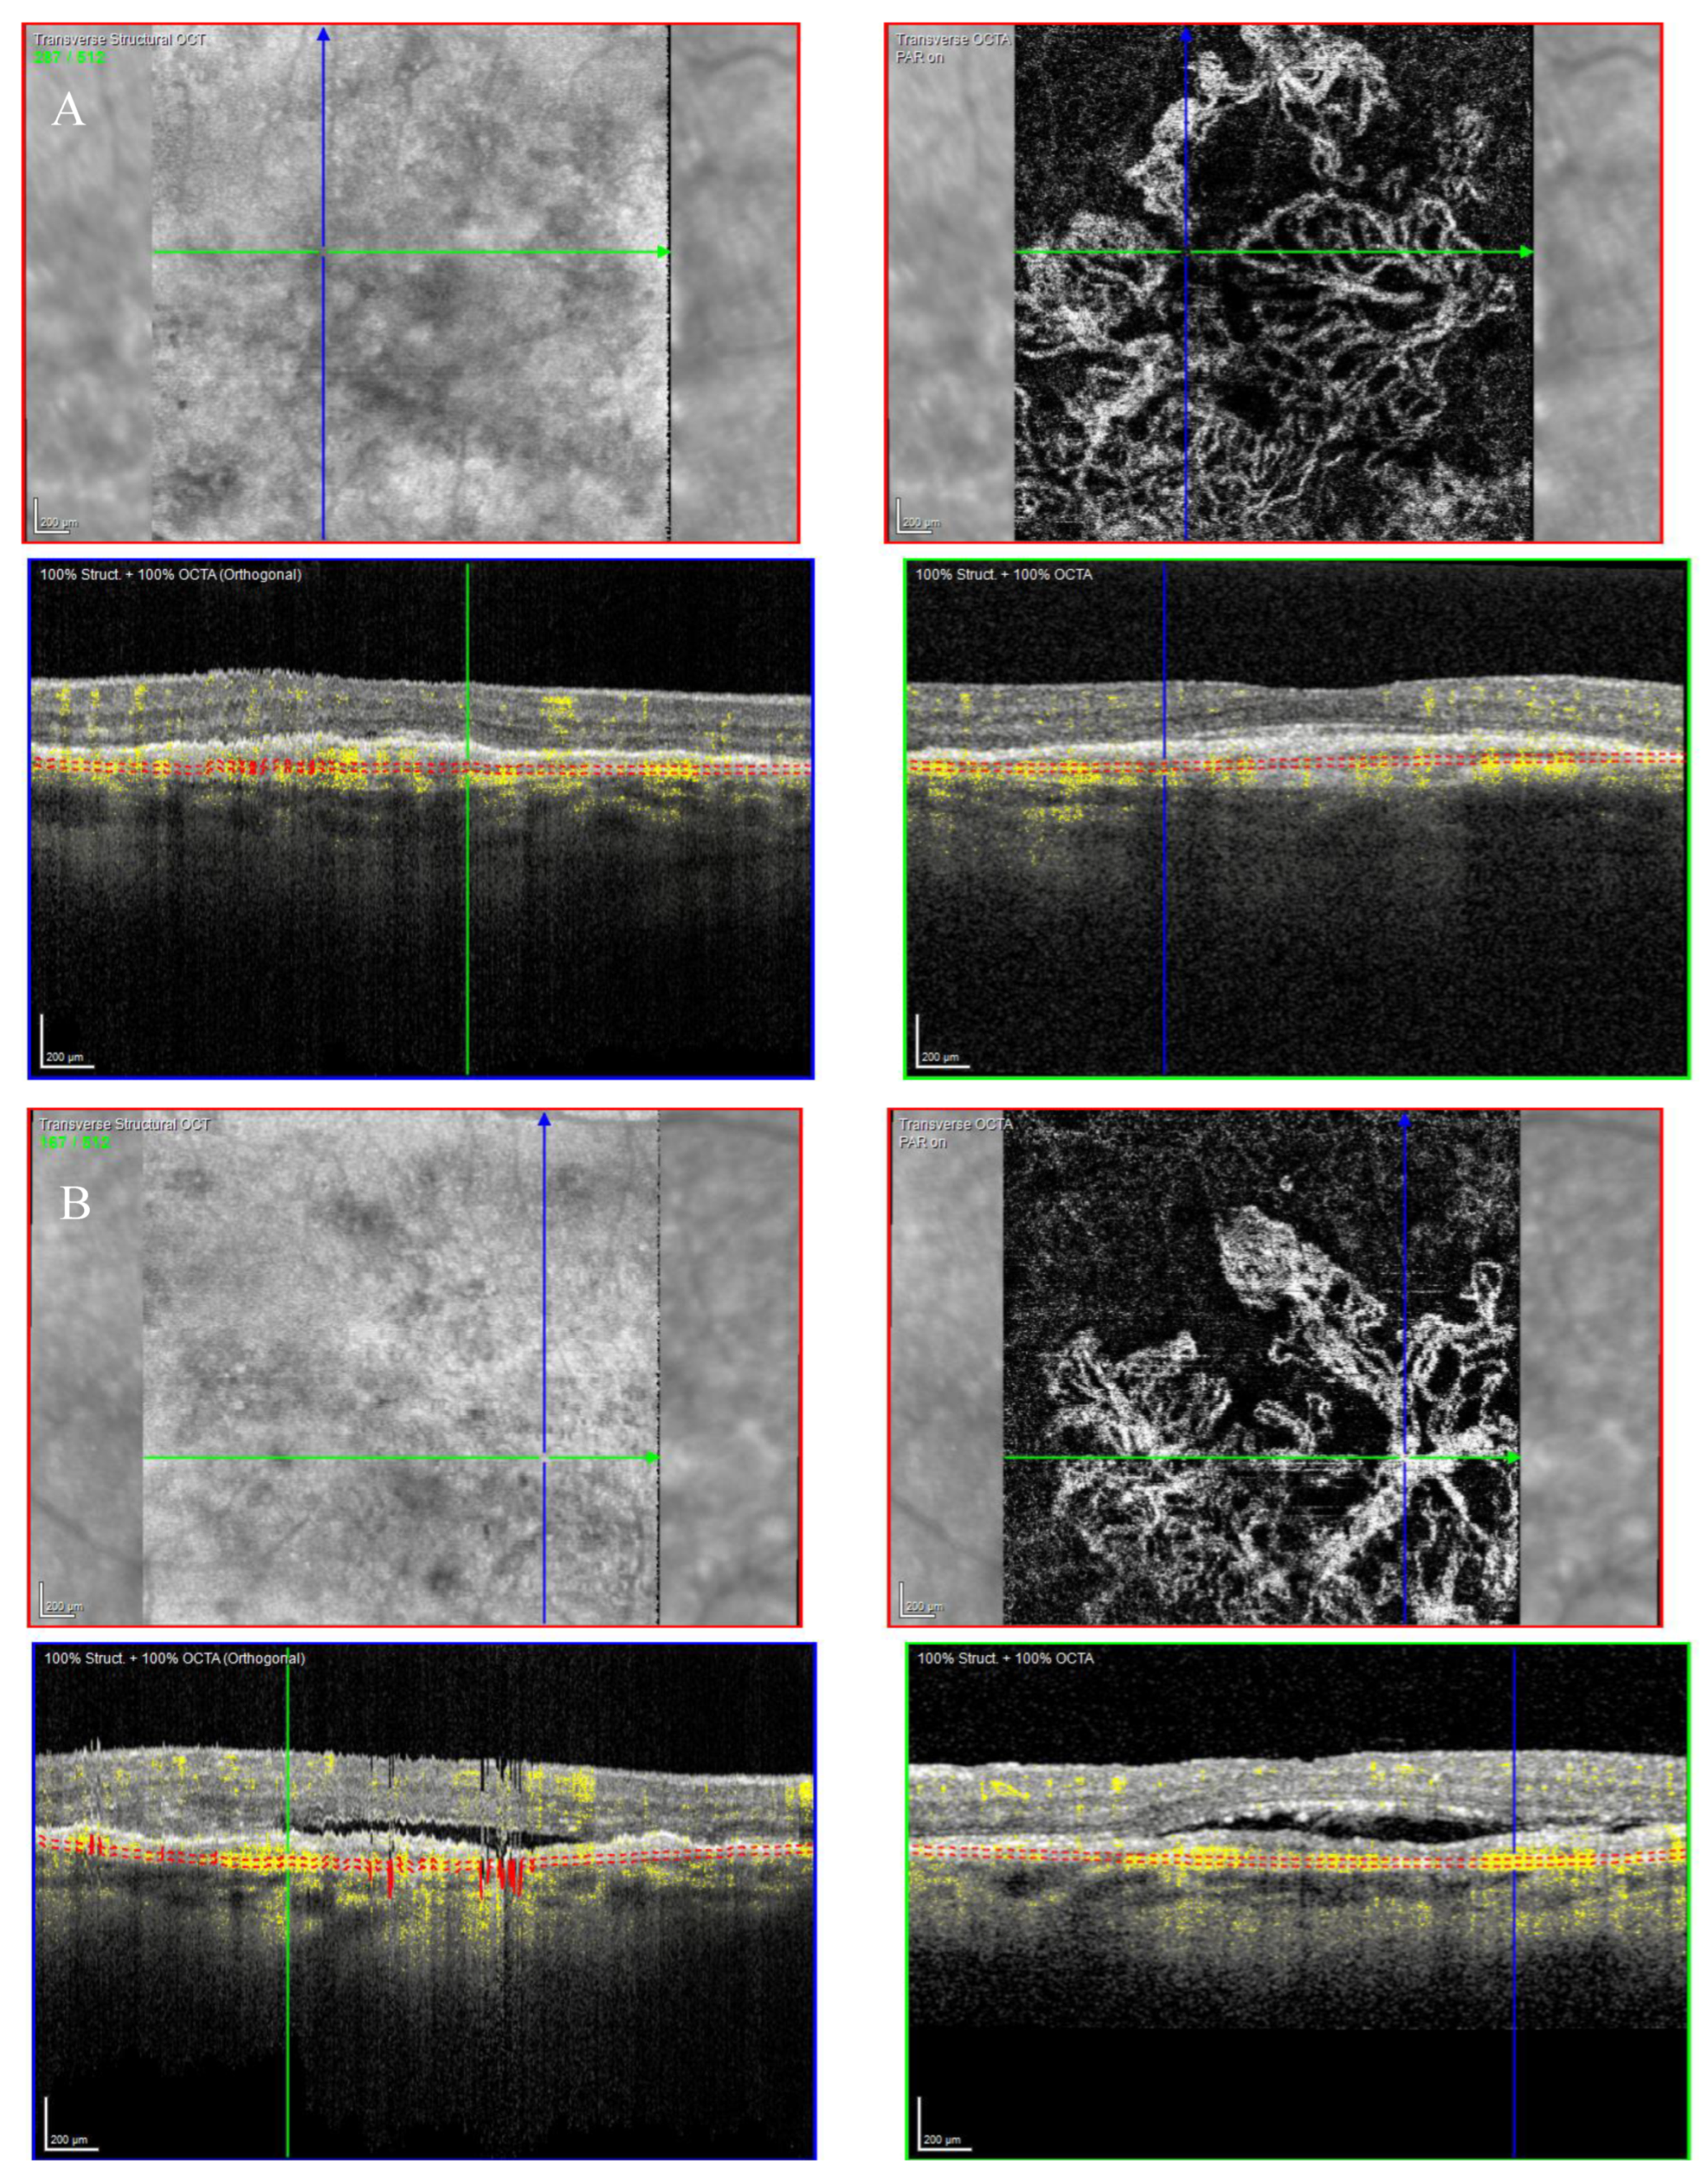

The OCTA scan confirmed the presence of MNV (Figure 7A,B).

Figure 7.

Case 5. Heidelberg Spectralis optical coherence tomography angiography shows a subretinal neovascular membrane in right (A) and left eyes (B).

The OCT showed a type 1 MNV with a fibrovascular PED, subretinal fluid, and BALAD in both eyes (Figure 6E,F).

Over the years, these features have shown improvement phases alternating to worsening ones.

The patient is still on treatment with anti-VEGF intravitreal injections (T&E regimen) for both eyes.

The BCVA has been stable throughout the treatment period. When last examined, it was 0.63 logMAR in the right eye and 0.32 logMAR in the left eye.